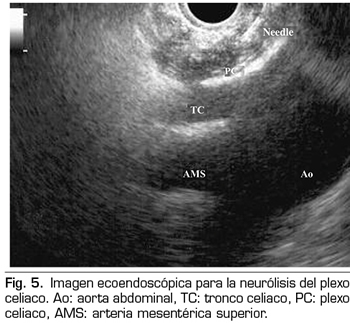

La ecoendoscopia ofrece la ventaja de una mayor visualización del plexo celiaco a corta proximidad, permitiendo una mayor precisión y seguridad en la administración del agente neurolítico y evitando la inyección en estructuras vasculares mediante el uso del Doppler (37) (Figura 5). No obstante, los trabajos que apoyan la neurólisis ecoendoscópica, considerada al igual que la técnica percutánea como una terapia de rescate, están limitados a estudios retrospectivos no controlados (38). Pauli y cols. publicaron un metanálisis que concluye que esta técnica consigue una reducción del dolor del 80 % en pacientes con cáncer de páncreas (39). Algunos estudios muestran un ligero descenso en el consumo de opioides, pero sin una fuerte evidencia científica.